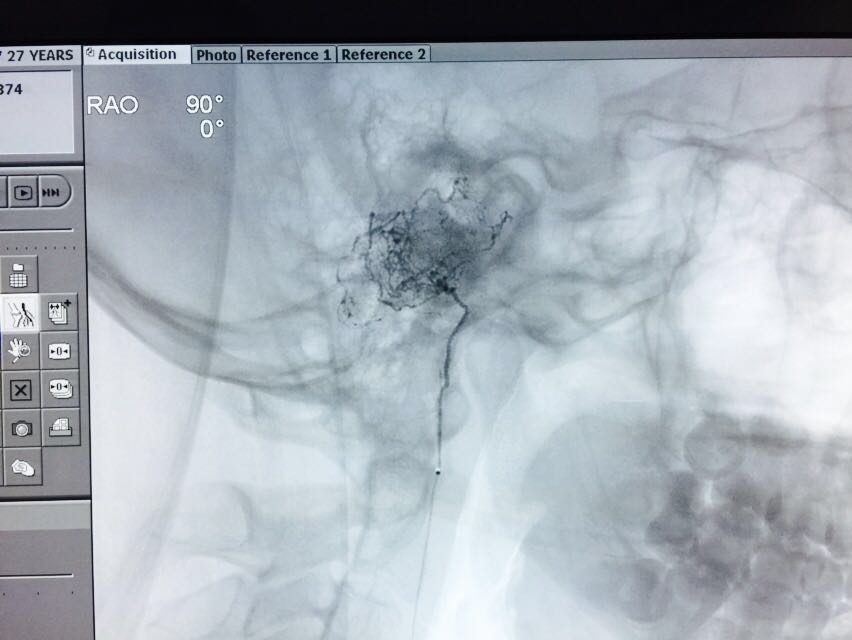

Bedah saraf vascular dan endovascular telah dilakukan untuk pengobatan semua variasi kelainan atau penyakit pembuluh darah, termasuk:

Arteriovenous Malformation (AVM)

melalui opsi/pilihan operasi mikro (microsurgery) maupun terapi minimal invasive (endovascular). Bedah saraf vascular dan endovaskular berusaha untuk memberikan pilihan terbaik dari salah satu tindakan itu atau kombinasi tindakan untuk menyembuhkan penyakit yang diderita.